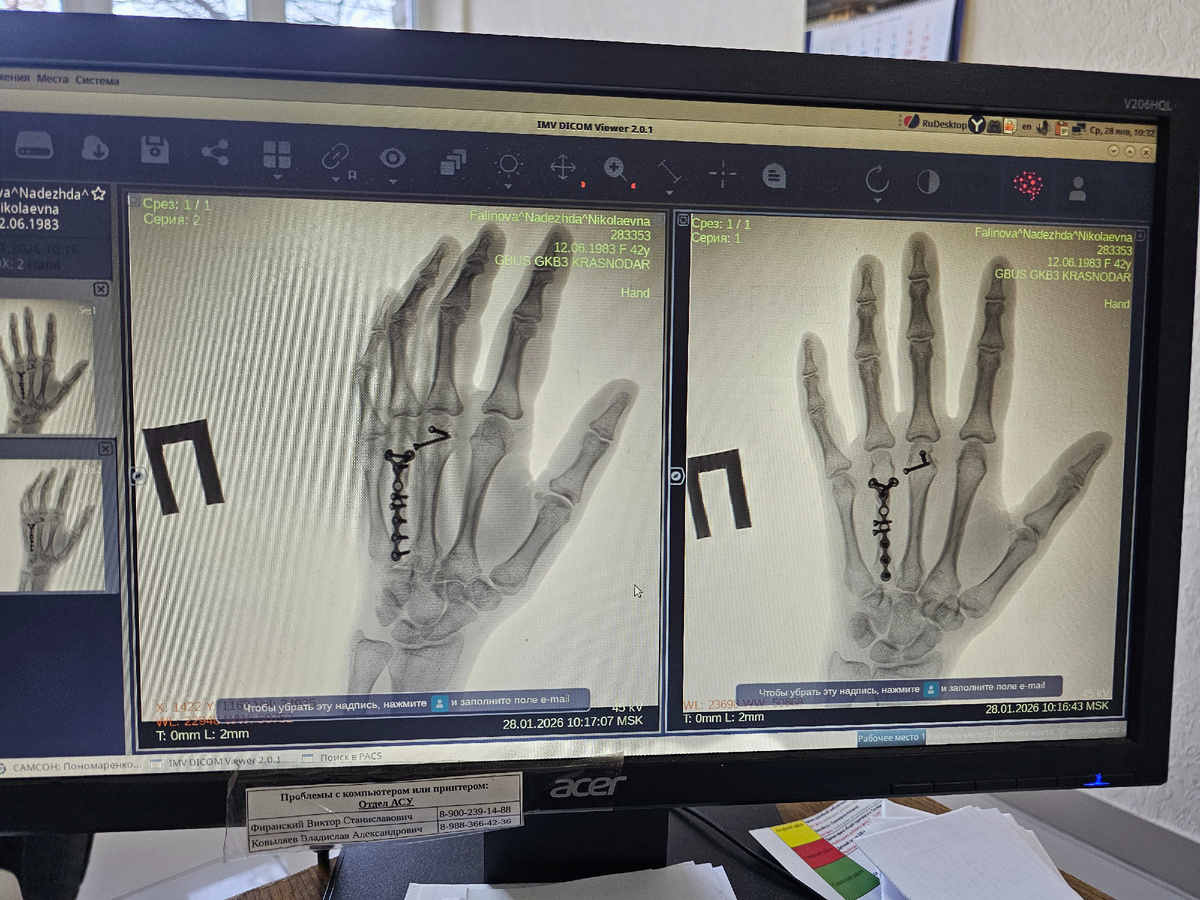

Даже не знаю за сколько времени я первый раз вышла на улицу. Погода у нас была та ещё..снег,мороз..боялась выйти куда-то, чтобы не поскользнулся. Но сегодня это было необходимо. Первый рентген после операции

Врач сказал,что срослось ,но при увеличении мне кажется не совсем🤔 Назначил лфк и фтл. В марте на повторный рентген и скорей всего на операцию снимать всю эту красоту🤦‍♀️